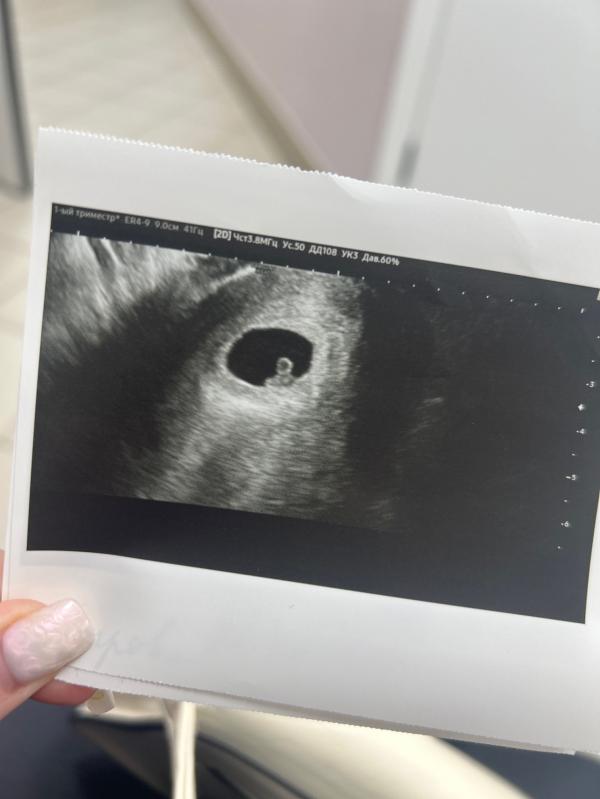

Развитие малыша в 6 недель и 5 дней: наши успехи

Мой малыш 🫶🏻 Тут нам 6 недель и 5 дней💕 Сердечко уже бьется👌 Растём😍